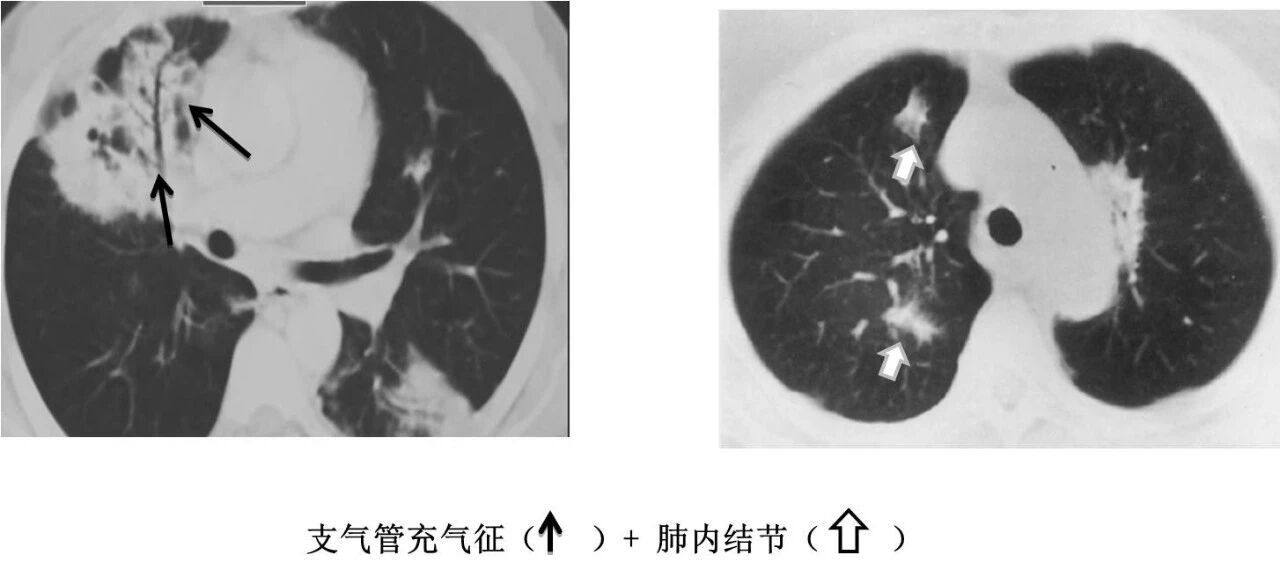

▶结节肿块型

MALT 的支气管扩张并无支气管管壁的破坏。由于淋巴瘤组织浸润导致肺泡塌陷,支气管周围实质破坏造成的,这类支气管扩张在肿瘤治疗后有时可消失。

肺粘膜相关淋巴瘤

结节、肿块,边缘模糊

充气支气管粗大、扭曲

▼伴有空气支气管征充气的支气管粗大、扭曲;